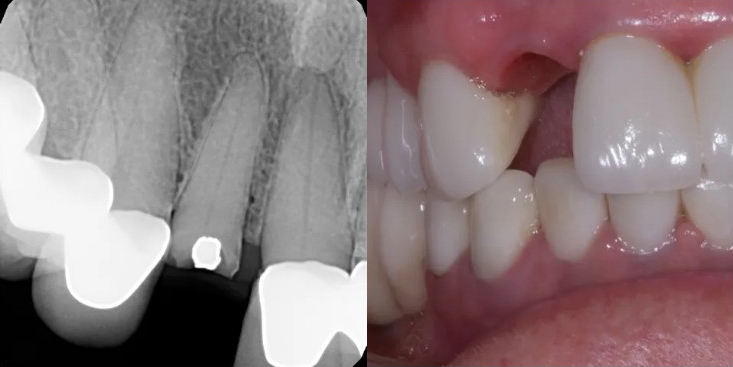

Before Treatment

After Treatment